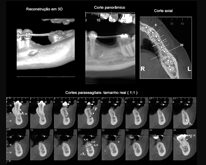

Tomografia Volumétrica

Planejamento de Implantes

Avaliação de enxerto ósseo;

Medidas de altura e espessuras ósseas.

Endodontia

Pesquisa de dilaceração/perfuração/fratura radicular;

Pesquisa de lesões.

Periodontia

Avaliação de perda óssea alveolar;

Avaliação de envolvimento endo-perio;

Envolvimento de furca.

Cirurgia Oral

Dente incluso e/ou supranumerário;

Terceiros molares, posicionamento e/ou relação com o canal mandibular/seio maxilar.

ATM

Visualização completa da região articular;

Verifica transtornos das articulações temporomandibulares.

Ortodontia / Odontopediatria

Avaliação das tábuas ósseas vestibulares e linguais;

Avaliação da relação dos dentes superiores

com o seio maxilar;

Avaliação da relação dos dentes inferiores

com o canal mandibular;

Avaliação da intercuspidação dentária.